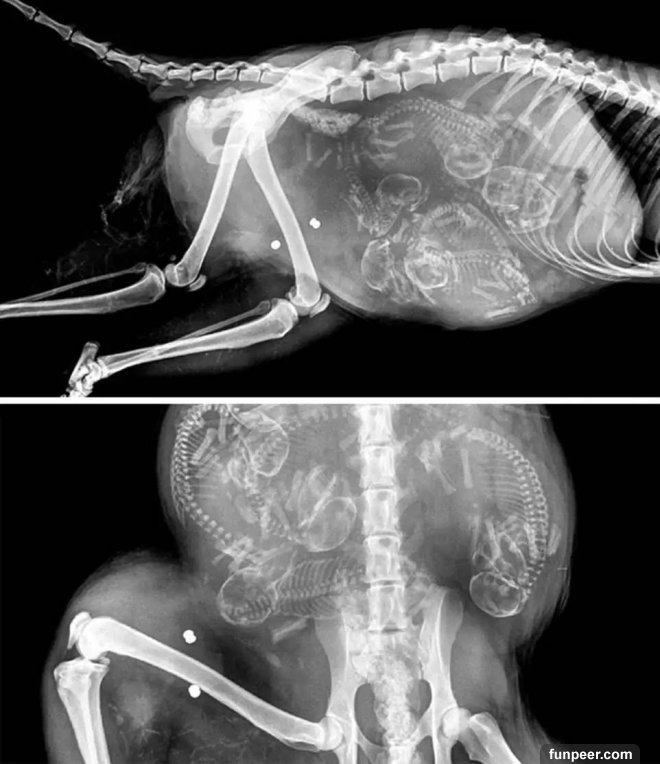

之前發過一部分動物懷孕後拍攝的X光照,最近照片又更新了,繼續來感受下: 這是一隻狗媽媽,數一下似乎是懷了七隻小狗

這兩張也是懷孕狗狗的X光照片